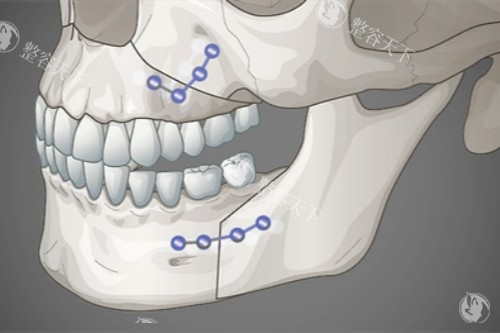

病例背景28岁女性因下颌角外翻导致"国字脸",伴有明显不对称,经何医生采用"长曲线截骨术"矫正。

手术过程术中同步进行咬肌修薄和颊脂垫调整,手术时长2.5小时,出血量仅80ml。

术中流程划线设计→消毒麻醉→小创口入路→骨骼重塑→止血缝合,全程心电监护。